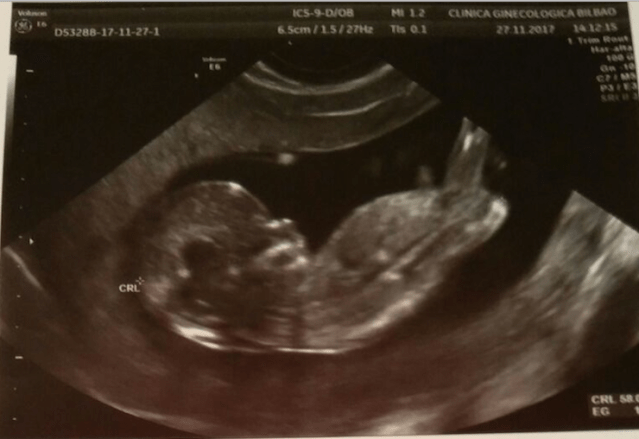

Os lo cuento desde el principio: el día 27 de noviembre teníamos nuestra cita con Cañas para la ecografía y el análisis que daba paso al segundo trimestre. Son unas pruebas importantes porque según mediciones y estadísticas delimitan un rango de probabilidades para diversos síndromes que podría sufrir el bebé. Nuestros resultados fueron muy muy buenos: 1 posibilidad entre 34.000 de Síndrome de Down y 1 entre 100.000 de Síndrome de Edwards. El pliegue nucal, la nariz y el latido del corazón estaban perfectos. El día 27 no nos dieron los resultados, evidentemente, así que nos quedamos en una pausa tensa hasta recibirlos una semana después. La ecografía fue larga y preciosa, el bebé no paraba de saltar, tenía dos brazos, dos piernas… se giraba todo el rato, le vimos de espaldas, de frente, la cara, el perfil… (era una ecografía normal de las 2D, pero está clarísimo que tiene mi nariz).